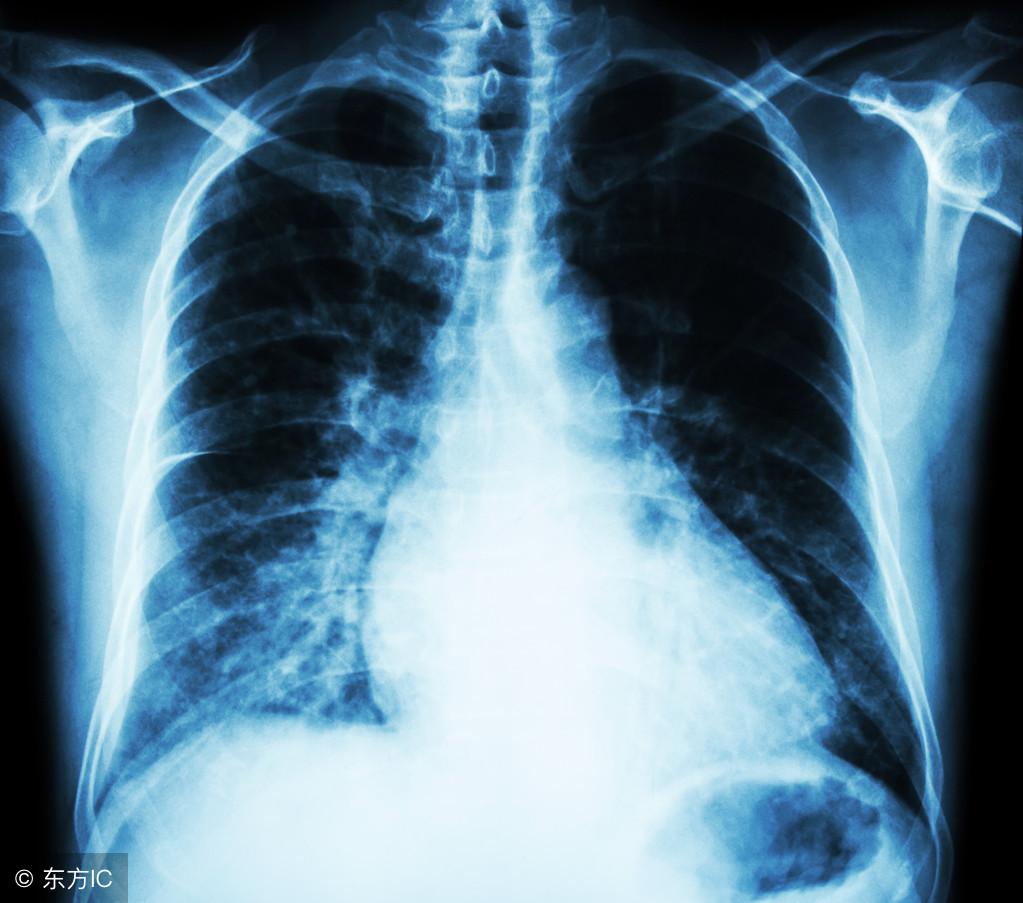

最后就是腺癌,发病率相对于前两者,还是相对比较低的,其中以女性最为多见,在腺癌早期的时候,多数是没有什么明显的症状的,往往是在做胸部x线的时候被检查发现,并且发展的速度也是比较慢的,所以治疗的效果相对于未分化癌来说,效果也是比较理想的一种。